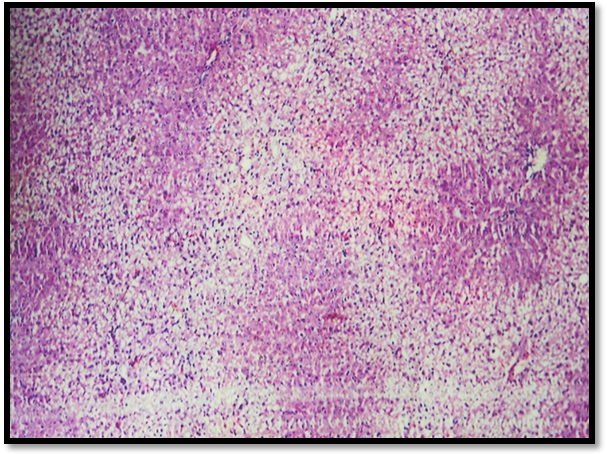

Histopathological observations

Histopathology of normal rat liver revealed prominent central view, normal arrangement of hepatic cells (Fig. 7). Microscopic examination of CCl4 treated liver section shows necrosis and fatty degeneration (Fig. 8). Liver section treated from Silymarin protected the structural integrity of hepatocyte cell membrane and recovery of hepatocyte cells (Fig. 9). Scopoletin treated group showed maximum recovery of hepatocytes, no fatty degeneration and necrosis and exhibited significant protection against CCl4 induced liver toxicity in rats (Fig. 10).

Photomicrographs of liver tissues of different groups of Albino rats

Fig. 8: CCl4 treated group